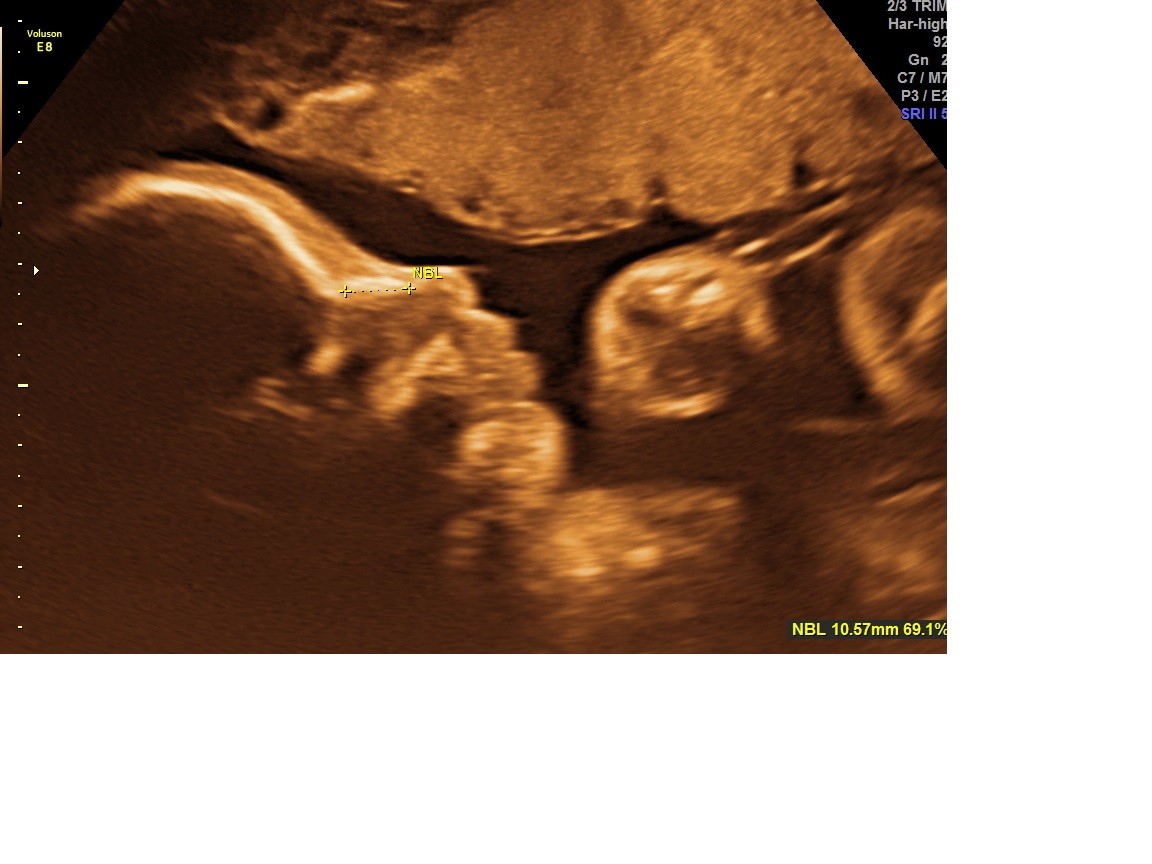

Ja już po usg. Lilka pozostaje Lilką

waży już 1350g. Ma nogi długie na 29 tyg, brzuszek na 28 tyg a inne wymiary na 27tyg czyli szczupła i wysoka po mamie

ułożona główkowo.

Taką ma buzię cudną